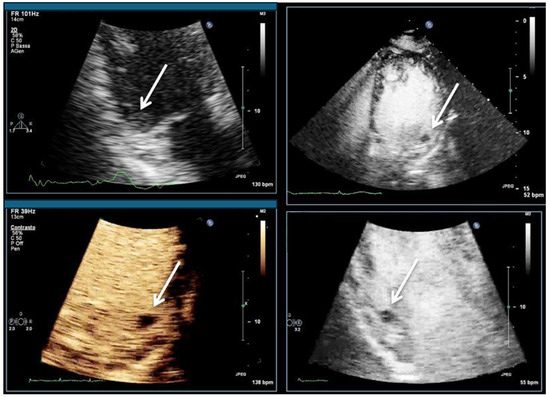

| Imaging method | Low-MI-contrast-specific imaging and intermediate-MI-contrast-specific imaging |

| Imaging planes | standard apical views additional zoomed views sweeps through the region of the suspected thrombus |

| Sector depth/width | Entire LV + 1/3 LA to assess global/regional LV function, zoomed views of the region with the suspected thrombus |

| Focus | At the depth of the suspected thrombus |

| Gain | Adjust to avoid obscuring the thrombus by intensive opacification of the cavity |

| Contrast application | bolus injections |

| Typical findings | 1. echofree mass 2. present in two different imaging planes 3. lump or laminar shape different from trabeculations’ documented size (two orthogonal diameters in at least one of the views), location, type (laminar vs. lump, single vs. multiple), surface (smooth vs. irregular) and mobility |

| DD tumor vs. thrombus | Opacified (vascularized) masses are suggestive of tumors; the vascularization can be demonstrated with myocardial perfusion imaging. CAVEAT: There are malignant tumors which appear avascular on CEUS. Tumors often are attached to normal myocardium. |

| Alternative imaging | Thrombi: Cardiac MRI when contrast echo is not possible or non-diagnostic, cardiac CT when cardiac MRI is not available Tumors: MRI provides tissue characterization and should be performed unless there is typical myxoma (attached to the interatrial septum) |